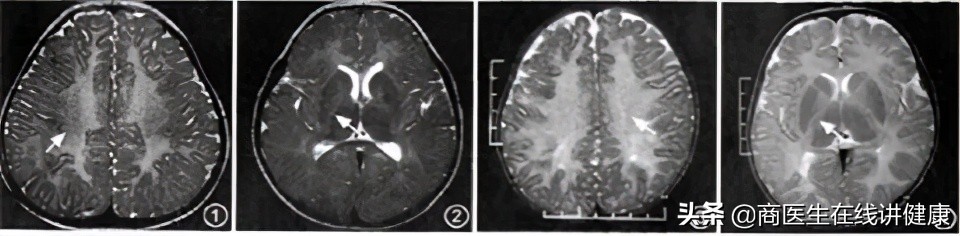

PMD的病理表现 为脱髓鞘区和髓鞘区相互交错,呈虎斑样状,镜下可以观察到有嗜苏丹样物质的沉积,且该物质沉积在脑干、小脑内以及半卵圆中心。 患者在患有佩梅病时,其病理性的特征通常表现为:脱髓鞘的病变;脊髓前角细胞、脑干神经核以及大脑运动皮质锥体细胞病变 。患者的病理性病变通常是由于病毒感染或患者的基因免疫异常所导致的。患者在患有PMD的同时,通产会患有PMD的并发症--髓鞘发育迟缓,该并发症会导致整个中枢瘫痪以及痴呆瘫痪多继发合并症,从而产生痉挛、疼痛,甚至会存在感染而危及生命的可能。

临床症状案例

摘取了几列关于PMD患者的临床症状案例,我们不难从图中看出,患者患病年龄较小,但确诊时间较长,但不难看出PMD患者的其临床首发症状表现通常为运动落后和眼球震颤的现象。